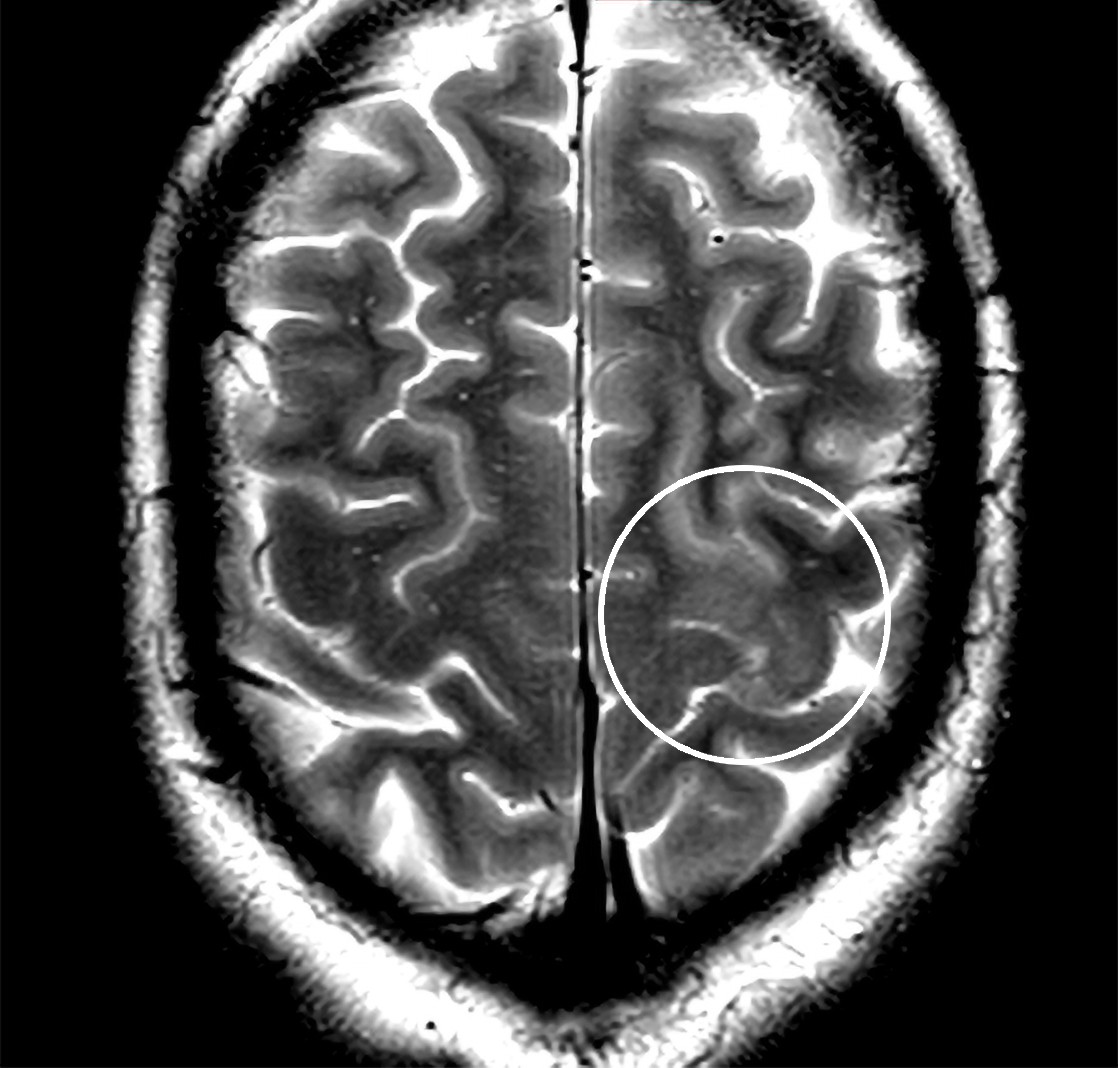

Dagen etter innleggelse i slagavdeling fikk pasienten på ny talevansker, beskrevet som dysartri med stakkatokarakter, samt lette sensomotoriske utfall i høyre overekstremitet med varighet på omtrent fem minutter. CT caput var fortsatt normal. MR caput uten kontrast med time-of-flight-angiografi tatt to dager etter innleggelsen viste antydning til diffusjonsinnskrenkning kortikalt og subkortikalt i primærmotoriske cortex i venstre frontallapp med beskjeden T2-høysignal-forandring samme sted (figur 1). Lesjonen var diffust avgrenset og derfor noe atypisk for hjerneinfarkt.

MR-funnet ble tolket av nevroradiolog. Det var ikke helt typisk for et kortikalt infarkt, men kunne være et resultat av tidlig trombolytisk intervensjon. Forandringer etter et epileptisk anfall kunne heller ikke utelukkes.